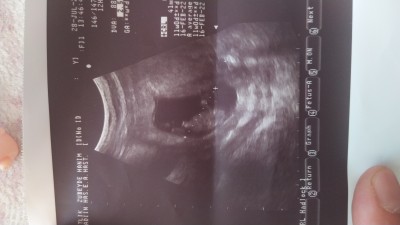

Cinsiyet tahmininde bulunur musunuz ?

Burda 11 haftalık di

Gebelik haftası 13+2